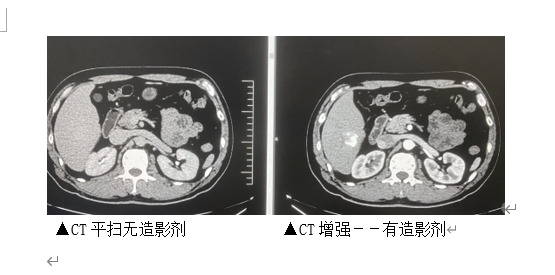

由于不同的器官、组织内血液的供应量和血流到达的时间不完全一致,因此增强的程度和时间也不完全相同,这样就可以使不同的组织或病变与邻近部位的密度差异变大,在X线下形成更鲜明的对比。所以注射造影剂并选择适当的时机进行CT扫描,可弥补普通扫描的不足,从而提高病变的诊断率。